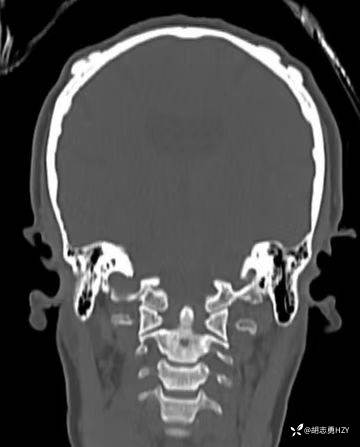

女性,45岁,家族性腺瘤性息肉病,额部顶部多发无痛性硬质包块